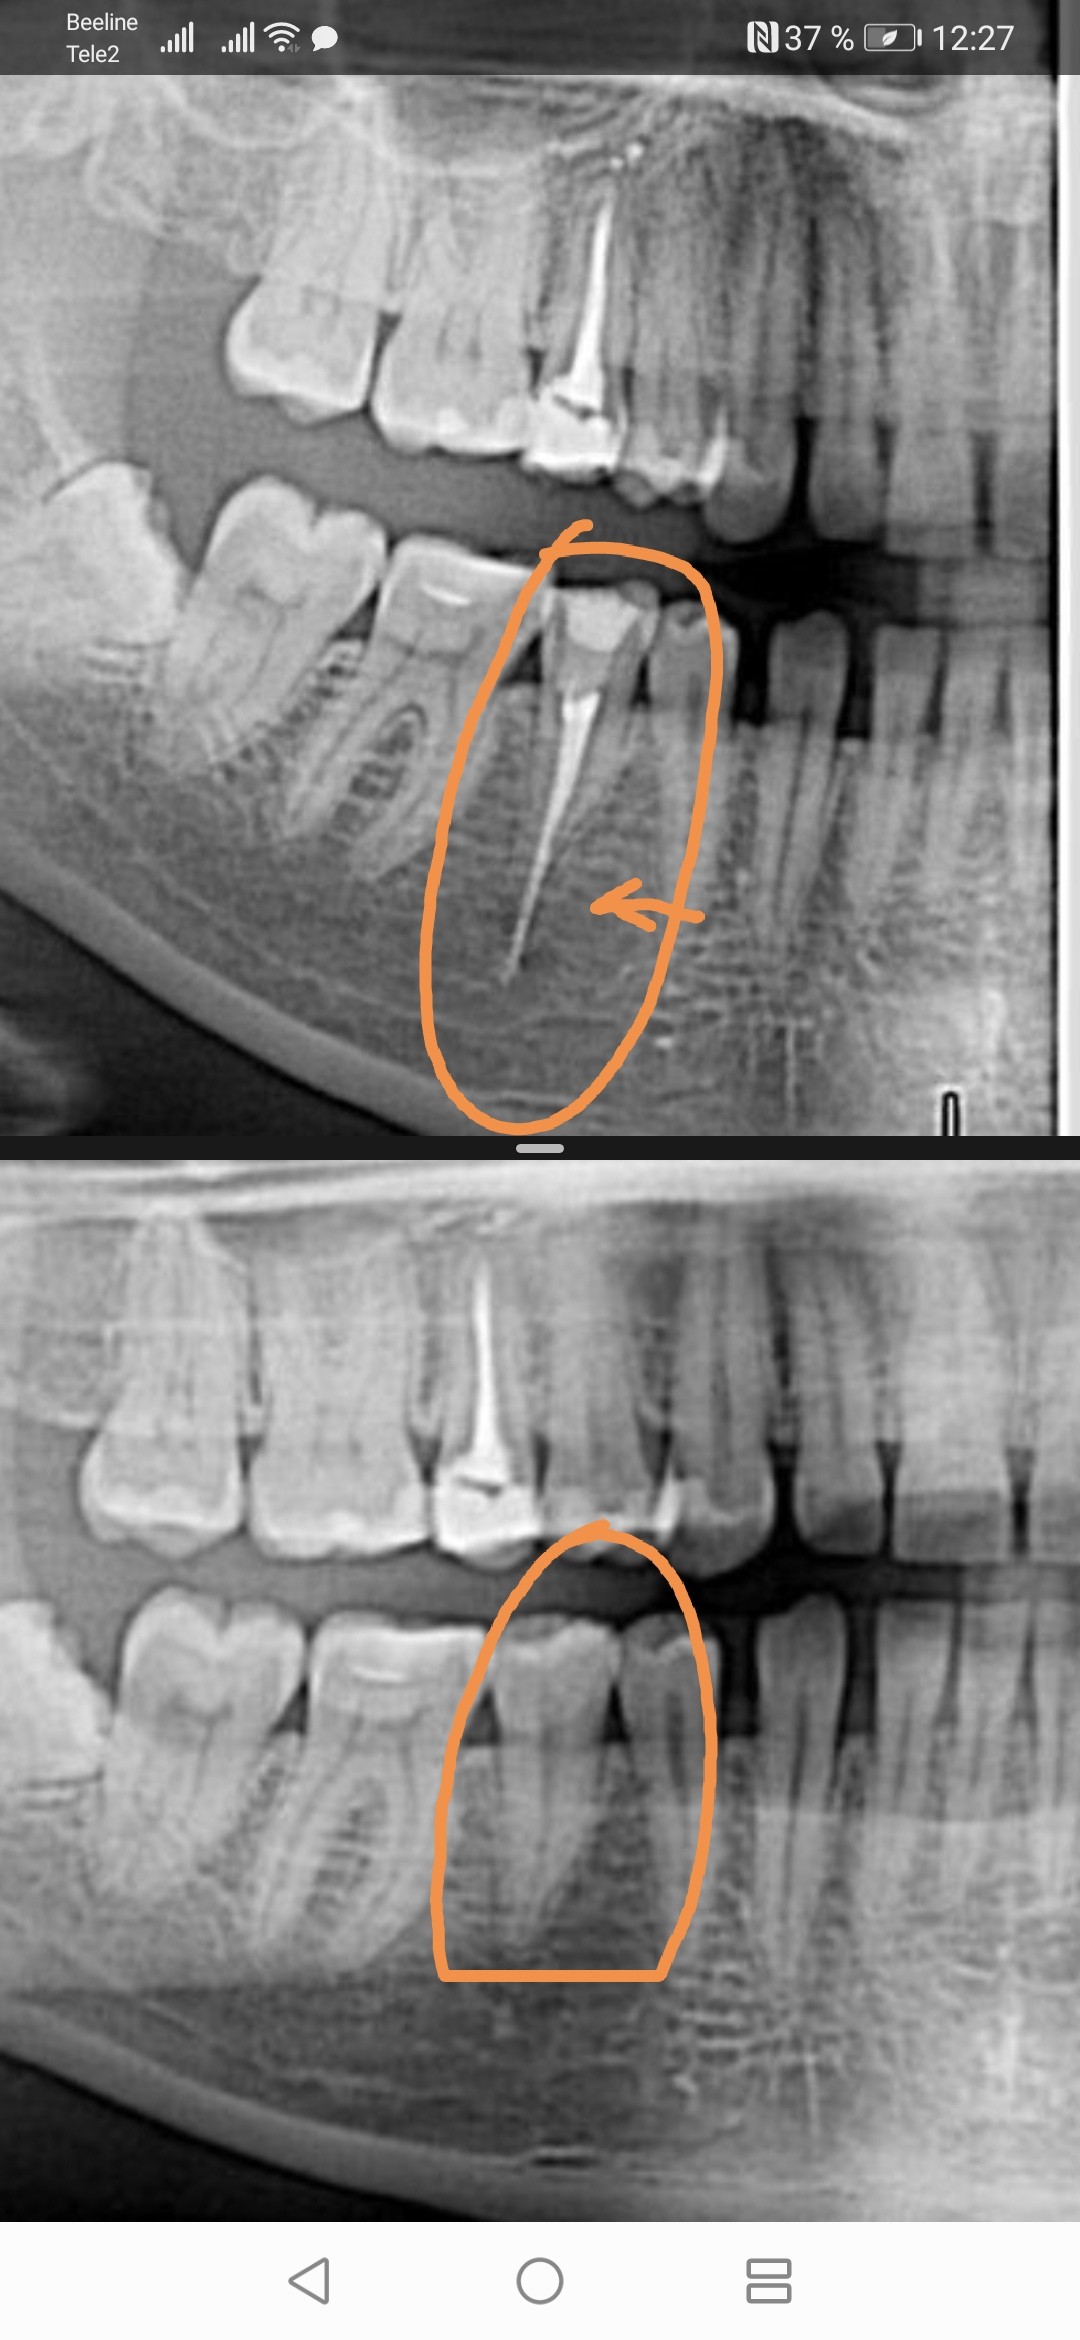

Обратитесь к стоматологу для рентгеновского снимка, чтобы определить точное расположение излишков пломбировочного материала.

Выведение материала при пломбировании корневых каналов в носовую пазуху.

Осложнения при лечении корня зуба

Как извлечь сломанный инструмент из корневого канала?

Осложнения при лечении пульпита. Попадание пломбировочного материала за пределы корня зуба

Пломбировочный материал в Гайморовой пазухе и что с этим делать. В конце готовлю плов ))))